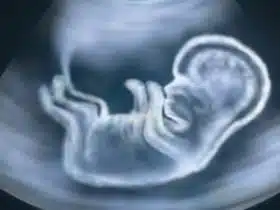

beba u trbuhu

Štucanje bebe u trbuhu

U trudnoći se događaju stalne promjene kako za trudnicu tako i za bebu u trbuhu. ...